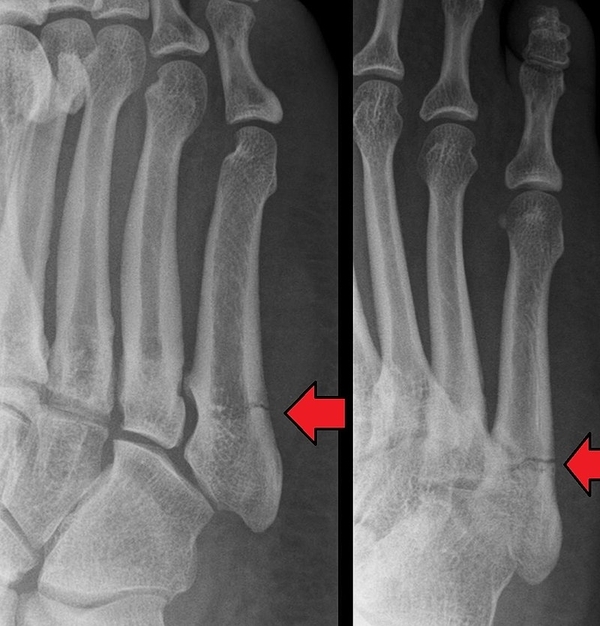

발목을 삐끗하거나 운동 손상, 외부 충격 등으로 인해 이곳에 통증이 나타났다면 반드시 주의해야 하는 것이 있습니다. 바로 골절인 것이죠.

이 부위는 단비골근 힘줄의 과도한 당김으로 인해 뼈가 조각나 떨어지는 견열골절(Avulsion fracture)이 잘 생깁니다.

존스골절(Jones fracture)라고도 하는데 심한 경우에는 수술을 필요로 하기도 합니다.